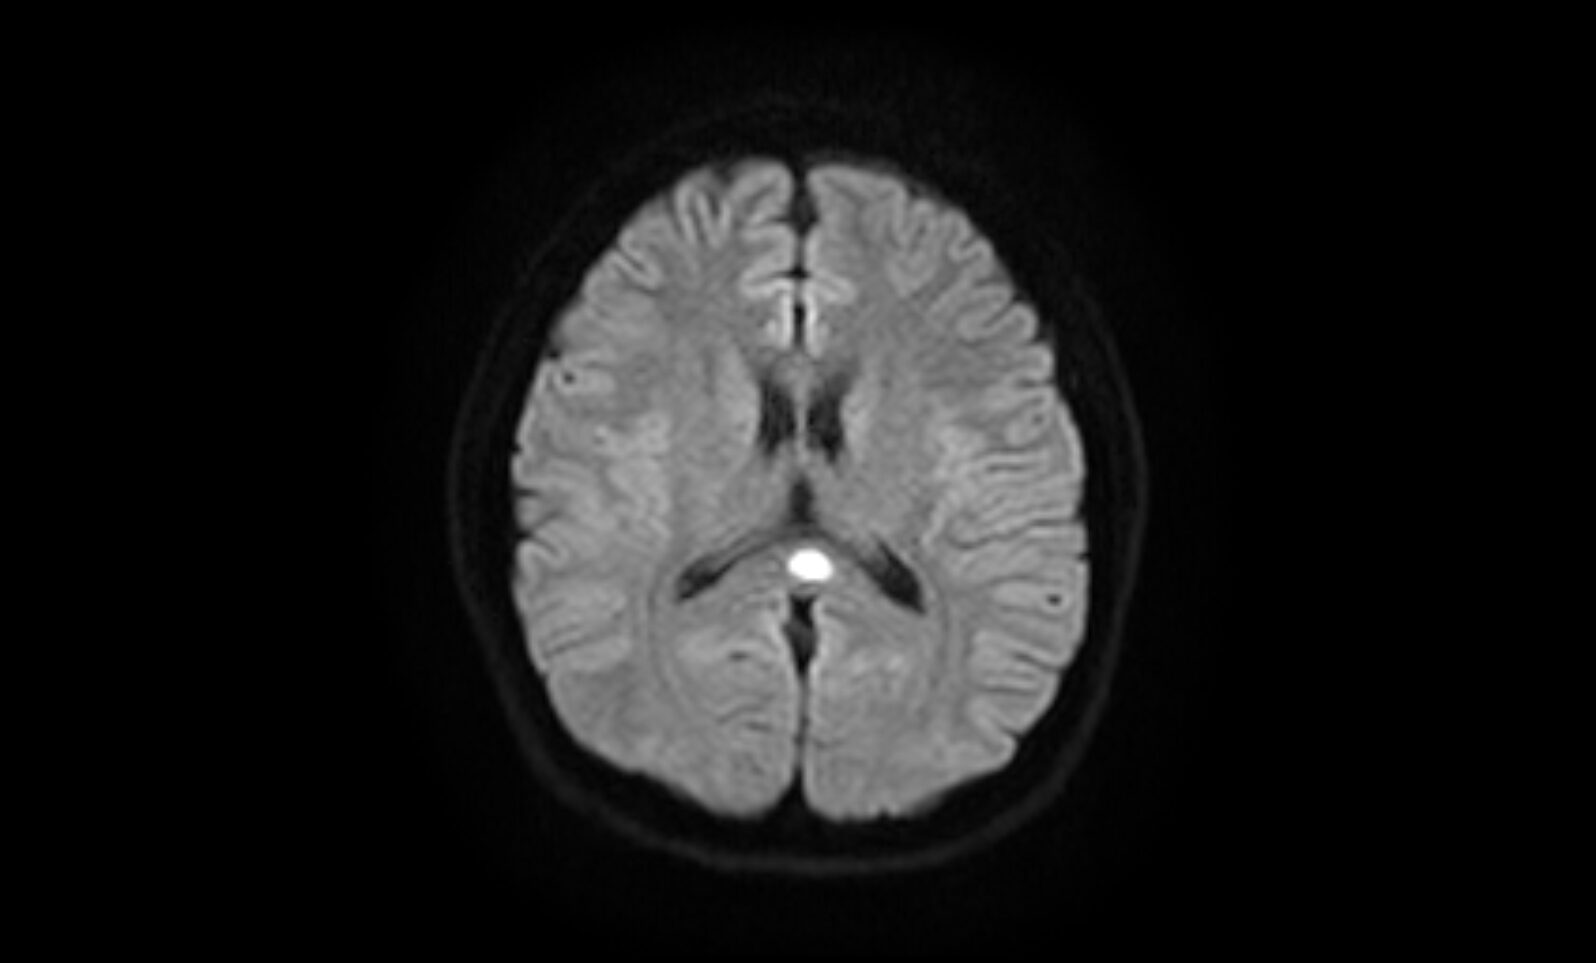

MERSについて

MERS(Mild Encephalitis Reversible Splenial lesion)といわれる、可逆的に脳梁膨大部に病変を見せる軽度脳炎症という疾患もあり、感冒後の頭痛で自覚症状に乏しいこともあります。MERSは基本的には後遺症はなく、予後は良好な疾患ですが、まれに痙攣や記憶低下などの症状を後遺することもあり、脳神経外科専門医における診断が必要となります。